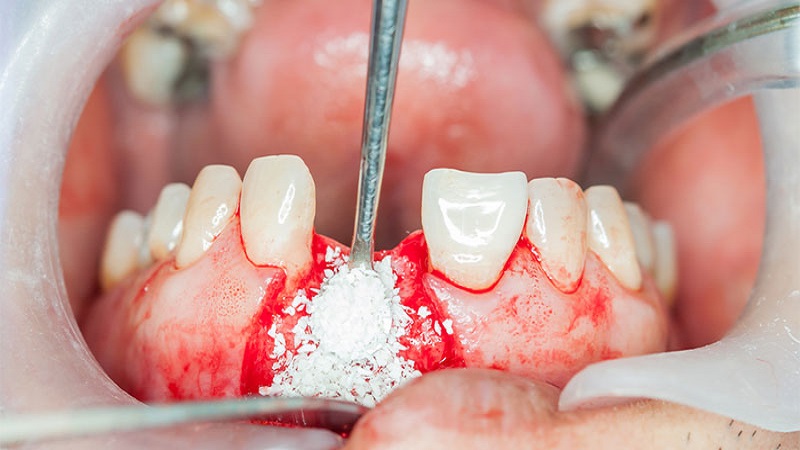

ضرورت انجام پیوند استخوان | پایه ایمپلنت دندان استخوان فک است. بههمیندلیل ، برای موفقیت و ماندگاری کاشت دندان باید تراکم استخوانی کافی در فک وجود داشته باشد. اگرچه عوامل مختلفی در موفقیت ایمپلنت دندان نقش دارند، اما یکی از مهمترین آنها استئواینتگراسیون (Osseointegration) بهمعنای همبندی با استخوان فک است.

در واقع استئواینتگراسیون فرآیندی است که در طی آن یک ماده زیستسازگار مانند پیچ تیتانیومی ایمپلنت بهخوبی با بافت استخوان متحد میشود. در نبود تراکم استخوانی کافی، این فرآیند نمیتواند انجام شود و ایمپلنت با شکست مواجه میشود.

مشکلیکه اغلب جراحان با آن مواجه هستند این است که بسیاری از بیمارانی که خواهان کاشت ایمپلنت دندان هستند از تحلیل و بدشکلی استخوان فک رنج میبرند. چنین مشکلاتی زمینه انجام پیوند استخوان برای ایمپلنت را فراهم میکنند. از عوامل موثر در تحلیل استخوان فک میتوان به موارد زیر اشاره کرد :